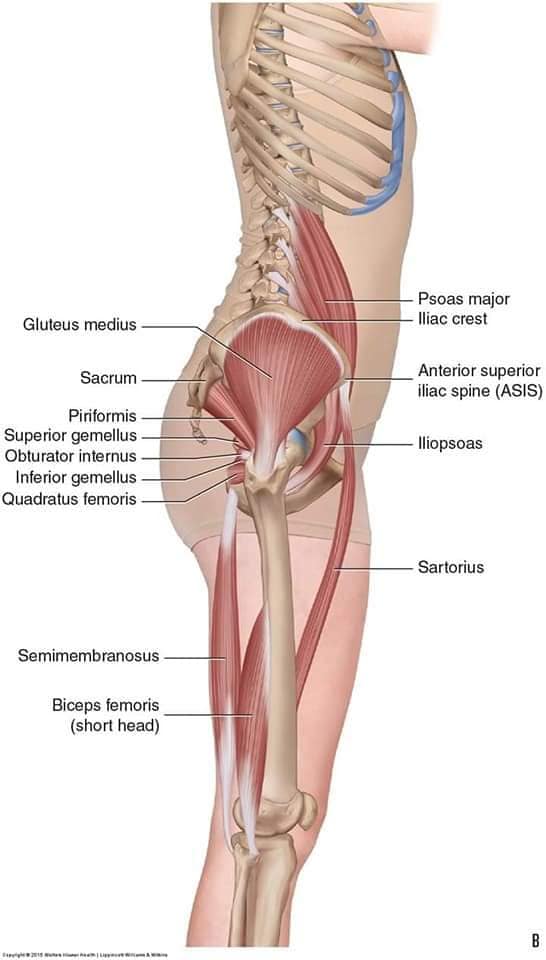

Скелетно-м'язова система людини (синоніми: Опорно-рухова система, опорно-руховий апарат, кістково-м'язова система, локомоторна система) — комплекс структур який утворює каркас, надає форму організму, дає йому опору та забезпечує захист внутрішніх органів і можливість пересування у просторі. Це функціональна сукупність кісток скелета, їх з'єднань (суглобів і сінартрозів), і соматичної мускулатури з допоміжними пристосуваннями, які здійснюють за допомогою нервової регуляції локомоції, підтримання пози, міміки та інших рухових діях, поряд з іншими системами органів утворює людське тіло.

Це саморушний механізм, який складається з 400 м'язів, 206 кісток і декількох сотень сухожиль. Більшість кісток скелету з'єднане рухомо за допомогою суглобів. Одним кінцем м'яз прикріплюється до однієї кістки, утворюючи суглоб, іншим кінцем — до іншої кістки. В англомовній літературі застосовують близькі за значенням терміни: англ. musculoskeletal system (скелетно-м'язова система) та англ. locomotor system (локомоторна система).

М'язова система людини є однією з основних систем організму, що відповідає за рухи, підтримання пози та стабільність. Вона складається з понад 600 м'язів, які можна класифікувати на скелетні, гладкі та серцеві м'язи. Скелетні м'язи, які є об'єктом нашого детального розгляду, дозволяють контролювати навколишній світ і виконувати різноманітні рухи. Особливу увагу в нашій статті буде приділено шейним і спинним м'язам, оскільки ці групи м'язів мають критичне значення для підтримання правильного постава та функціонування хребта.

Скелетні м'язи з'єднані з кістками за допомогою сухожиль і відповідають за більшість волевих рухів. Вони поділяються на:

Скелетні м'язи мають поперечну смугасту структуру, що забезпечує їхню здатність до швидкого і ефективного скорочення.